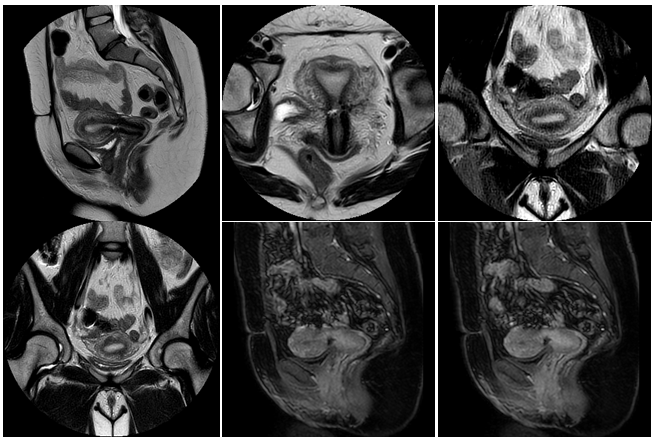

The REI workup included ultrasound, hysterosalpingogram (HSG), MRI and hysteroscopy with lysis of adhesions, and endometrial sampling for evaluation of failed intrauterine insemination, 6 months prior to referral. The initial ultrasound showed mucus accumulation and free fluid in the uterus (Figure 1). Hysteroscopy revealed a small out-pouching in the lower anterior uterine segment. A subsequent MRI in our clinic confirmed both the ultrasound and Hysteroscopic findings, revealing a small CSD, (Figure 2) for which she desired surgical correction.

Figure 2 Patient 1, MRI: The anteverted uterus measures 8.2 x 5.8 x 3.9cm. The myometrial junctional zone is normal in caliber measuring 0.6cm. The endometrial stripe is normal measuring 1.1cm. There is a low anterior transverse cesarean section scar. There is a small dilatation of the right cesarean section scar measuring 0.8 x 0.5 x 0.2cm likely an isthmocele